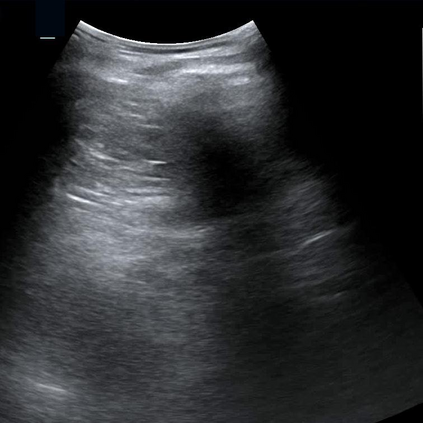

Most deep neural networks (DNNs) based ultrasound (US) medical image analysis models use pretrained backbones (e.g., ImageNet) for better model generalization. However, the domain gap between natural and medical images causes an inevitable performance bottleneck. To alleviate this problem, an US dataset named US-4 is constructed for direct pretraining on the same domain. It contains over 23,000 images from four US video sub-datasets. To learn robust features from US-4, we propose an US semi-supervised contrastive learning method, named USCL, for pretraining. In order to avoid high similarities between negative pairs as well as mine abundant visual features from limited US videos, USCL adopts a sample pair generation method to enrich the feature involved in a single step of contrastive optimization. Extensive experiments on several downstream tasks show the superiority of USCL pretraining against ImageNet pretraining and other state-of-the-art (SOTA) pretraining approaches. In particular, USCL pretrained backbone achieves fine-tuning accuracy of over 94% on POCUS dataset, which is 10% higher than 84% of the ImageNet pretrained model. The source codes of this work are available at https://github.com/983632847/USCL.

翻译:大部分深心神经网络(DNNS)基于超声波(美国)的超声波医学图像分析模型使用预先训练的脊椎(如图像网络)来进行更好的模型化分析。然而,自然图像和医疗图像之间的领域差距造成了不可避免的性能瓶颈。为了缓解这一问题,为在同一领域直接训练建造了一个名为US-4的美国数据集。该数据集包含来自四个美国视频子数据集的23 000多张图像。为了从美国-4中学习强健的特征,我们提议了美国半监督的对比学习方法,名为USCL(USCL),用于预培训。为了避免负面对子与有限的美国视频中丰富的地雷视觉特征之间的高度相似性,USCL采用了一种样品配对生成方法来丰富单步对比性优化所涉及的特征。关于一些下游任务的广泛实验显示了USCL对图像网络预培训和其他状态艺术预培训方法的优势。特别是,USCLU预先训练的骨架在POCS数据集上实现了94 %的微调精准性精确度,这在图像网络上比84%高10 %/MUSPASTASTASTRAIN premstrain practresmex pract press press rodustrismex sramduction sramduction sramduction sramduction surgles)。